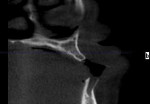

The 45-year-old female patient presented seeking a replacement for an unsatisfactory maxillary denture that she had received 2 years earlier, after extraction of her last remaining maxillary teeth (Figure 1). A smoker, she underwent clinical and radiological examination that revealed bilateral sinus pneumatization. Her premaxilla was angled, with a pronounced buccal undercut. A computed tomographic (CT) scan confirmed the buccal concavity and the slope of the premaxilla (Figure 2).

Immediately after implant placement, a panoramic radiograph was taken (Figure 11). It confirmed that none of the implants were impinging on the sinus cavity. A postsurgical CT scan (Figure 12) confirmed that placement of the 20-degree angled implants followed the natural slope of the maxillary ridge, creating adequate prosthetic space.